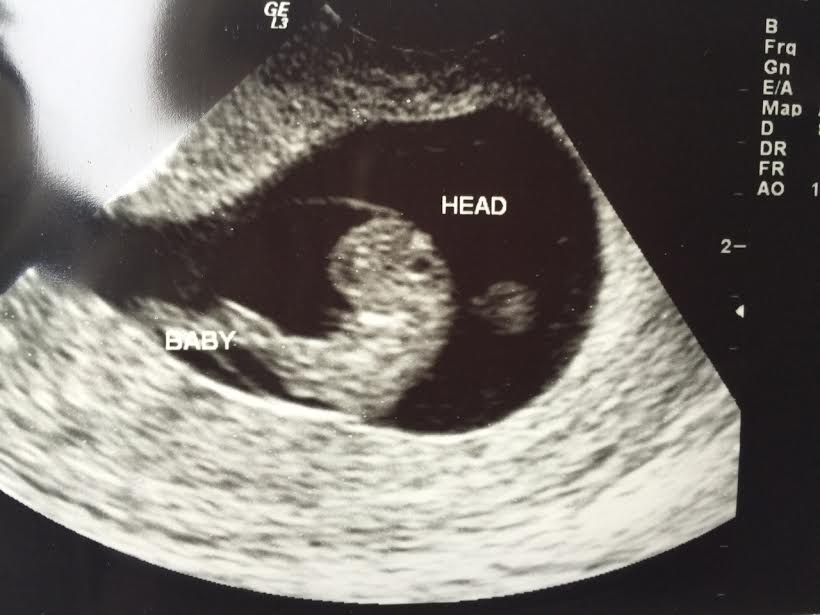

Great news! Miles and I are having a baby! Due in late November. Mo went with me to the Ultrasound. Look at that little beauty. It’s a missionary in the making.

Super fine Missionary in the making w earlobes n eyelids!!